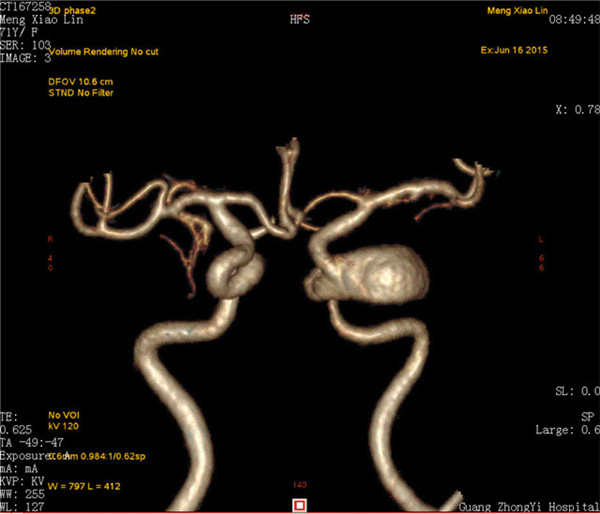

患者是一位70岁的女性,已视物重影1年余,经外院检查确诊为“左侧颈内动脉海绵窦段巨大动脉瘤伴瘤内血栓形成”,医生告知因动脉瘤位于海绵窦内,瘤颈宽约8mm,大小约2.8×2.3×2.2cm,传统手术方法无法完成动脉瘤夹闭或栓塞治疗,同时手术创伤大、风险高。听了医生的话患者不得不放弃手术。

最近,患者因症状加重来到YABO鸭脖第一附属医院求治。该院神经外科张高炼主任主持的治疗团队对该病例进行了讨论和分析,因影像学检查显示动脉瘤载瘤动脉明显迂曲且血管直径较细小,覆膜支架系统通过可能较困难且易引起载瘤血管损伤或动脉瘤破裂出血,他们决定利用密网支架技术行颅内巨大动脉瘤封堵技术为患者治疗。新技术的开展经汇报后得到院领导的大力支持,医院为此简化医疗药械申购手续,购买由美国eV3公司生产的Pipeline血流导向装置(密网支架系统),并邀请到中美合作上海德济医院院长宋冬雷教授前来会诊和指导。

术前CTA